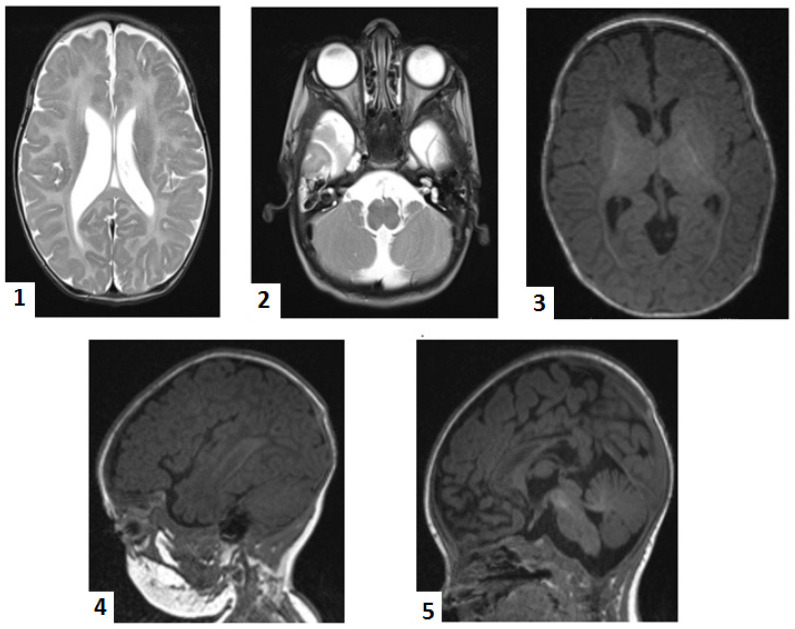

At 2 months, brain magnetic resonance imaging (MRI) showed bilateral perisylvian polymicrogyria, delayed partial myelination of the posterior limb of the internal capsule, cerebellar atrophy (central lobule and culmen) with secondary mega cisterna magna, callosal dysgenesis, and bilateral temporal subarachnoid cysts (Figure 1). These findings led us to suspect a rare neurodegenerative disorder. We then performed a genetic test on the patient’s buccal swab using whole-exome sequencing (Blueprint Genetics Whole Exome Plus Test version 2, Espoo, Finland, 9 February 2018). The results showed that the patient had two homozygous mutations: HSD17B4 c.788del.p(Pro263GInfs*2) (NM_000141.4) and SUOX c.913G>A, p.(Ala305Thr)(NM_000456.3). Upon searching in genetic databases (ClinVar, gnomAD, HGMD), it was found that the HSD17B4 variant was previously reported once as pathogenic in ClinVar [ref. 10]. However, the SUOX variant, although previously reported once in the heterozygous variant in gnomAD, was predicted as deleterious by some in silico tools, including PolyPhen and MUTTASTER. Technical details on WES workflow are presented in the Supplementary Materials. We offered genetic counseling to the parents and stopped further biochemical confirmation of the D-BPD. This decision was taken as the extended metabolic screening and all of the genetic tests performed up to this moment were supported by a non-governmental charity organization. Given the lethal outcome, the parents refused other investigations.

We could rule out Pompe disease and SMA by accessing free tests. However, not even routine genetic testing is not covered by the state Health Insurance House in Romania. As the infant’s seizures worsened and became more frequent and difficult to control, a non-governmental charity organization helped to conduct a genetic test for epilepsies, which also came back negative. Repeated cranial ultrasounds during the neonatal period showed non-specific aspects, prompting an MRI at two months. The MRI results suggested rare neurodegenerative disorders. The MRI scan was extremely helpful, providing crucial information, as there are reports of D-BPD cases with normal imaging aspects [ref. 3,ref. 20,ref. 35]. Germinolytic cysts are relatively common neuroimaging findings in D-BPD [ref. 4,ref. 18,ref. 35].

Whole-exome sequencing revealed that our patient was homozygous for the variant HSD17B4 c.788del, p.(Pro263GInfs*2). The variant is absent in gnomAD but is reported in ClinVar. The defect is located on exon 12 and consists of the deletion of a base pair, generating a frameshift that prematurely stops codon2 amino acids downstream. The variant predicts either a truncation of the encoded protein or the absence of the protein, a common mechanism for disease [ref. 38]. Consequently, the patient was classified as having type I D-BPD, which matches its severe phenotype. Ferdinandusse et al. [ref. 9,ref. 11] proposed a genotype–phenotype correlation, as the depicted residual activity of D-BP was associated with less severe phenotypes in their cohort, and the mutation effect on the protein structure may predict the phenotype. This homozygous variant was previously described in 2006 in the cohort of Ferdinandusse et al. [ref. 9] and classified as pathogenic and associated with D-BPD (PMID 16385454). An unpublished observation in ClinVar reported an association of the same homozygous mutation in a patient with polymicrogyria, partial callosal agenesis, congenital hypotonia, epilepsy, developmental delay, dysmorphic features, anemia, and abnormal eye movement [ref. 38]. Other laboratories also detected the variant in the context of clinical testing (variation ID 632859 in ClinVar) [ref. 38]. Similarly, congenital hypotonia, epileptic seizures, polymicrogyria, callosal dysgenesis, and severe psychomotor delays were found in our patient.